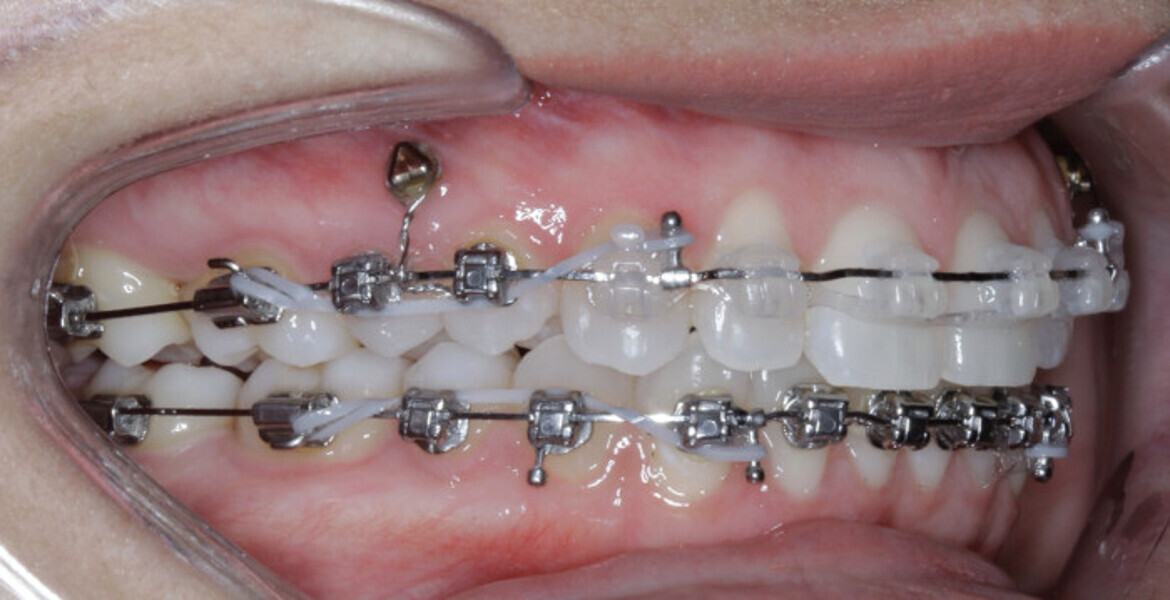

New Age orthodontics and orthopaedics with temporary anchorage devices